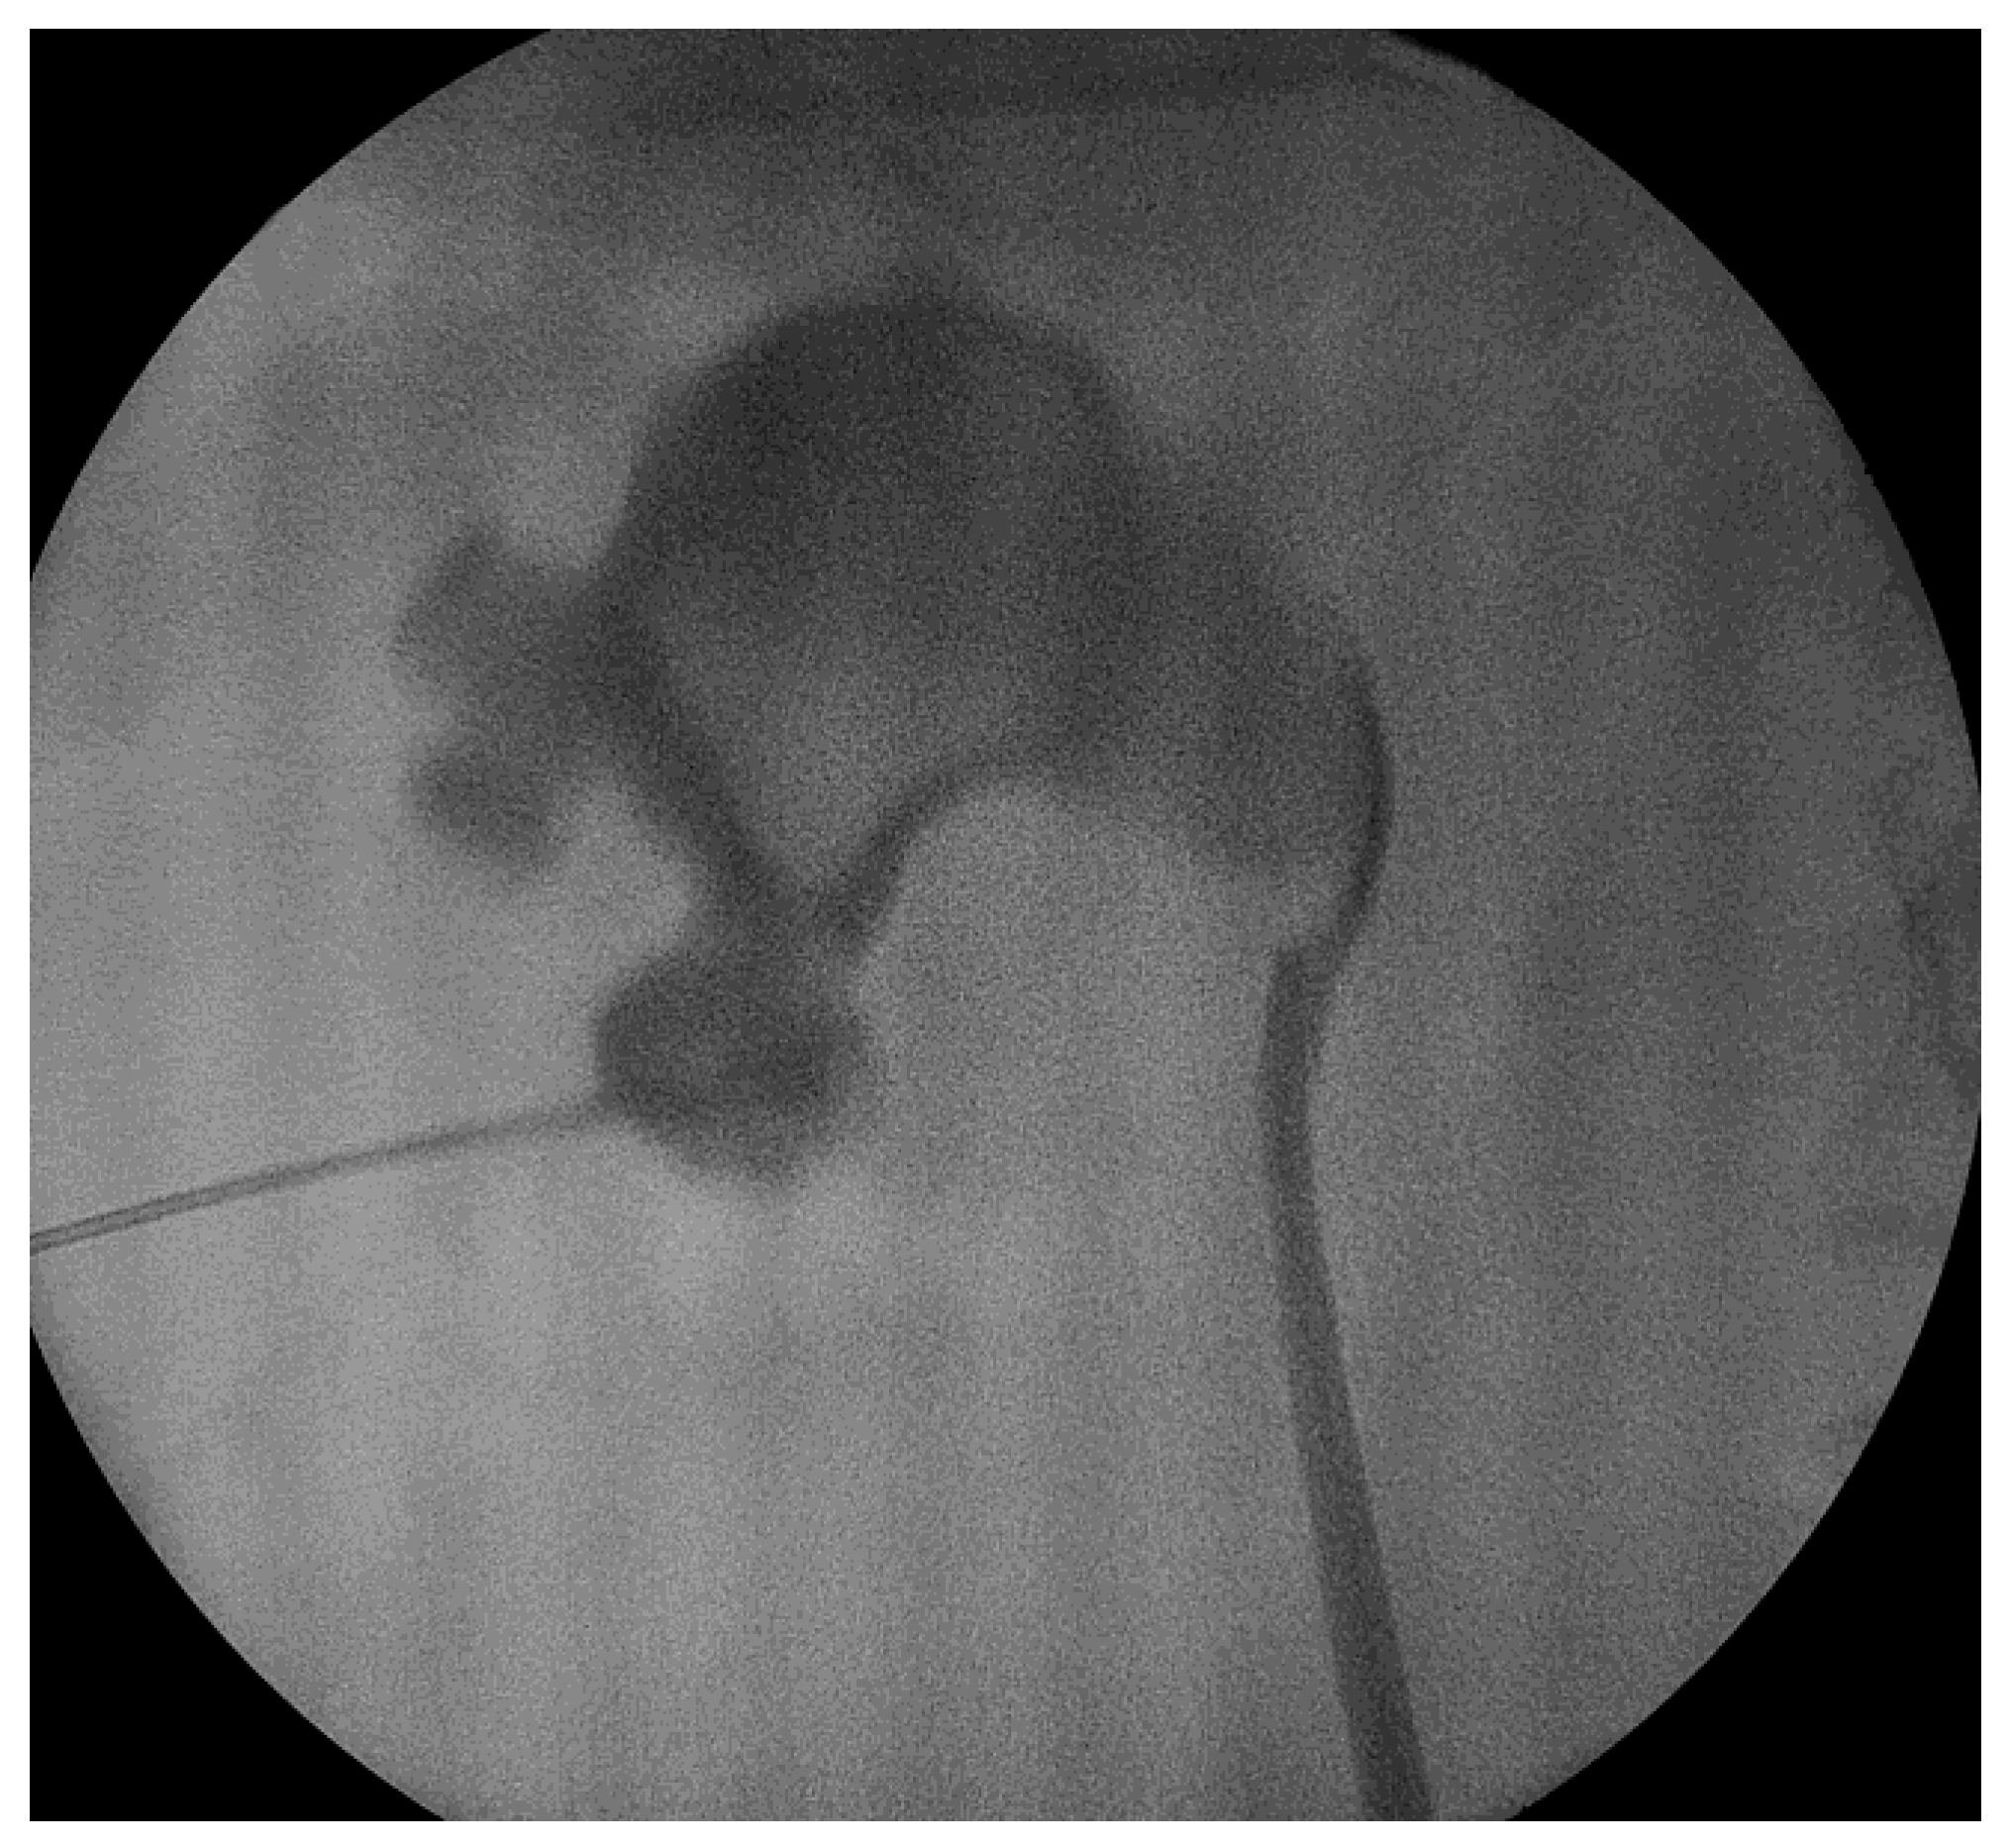

The procedure was conducted under spinal or general anesthesia. The patient was positioned in the lithotomy position, then a 5-Fr ureteral catheter was inserted through the ureter. The patient was then moved to a prone position and the calyceal system morphology was evaluated via fluoroscopy using a contrast medium. Access was gained to the desired calyx using an 18 G needle under fluoroscopy unit monitoring. As a rule of thumb, the approach of the kidney, dilation and sheath insertion are very similar to regular PCNL. Access to the collecting system was achieved through the lower posterior calyx; alternatively, the calyx with the largest stone burden or the calix promising access to most of the stones were targeted [7,8,9]. As an alternative technique, renal access was obtained under ultrasonographic guidance, still in a prone position, in some cases. This did not have any impact on the operative technique itself or the overall duration of the intervention.

After that, a 0.035-inch hydrophilic guide wire was inserted into the collecting system. Dilation was performed using Amplatz dilators, and a 16 Fr Amplatz sheath was inserted. We used a 15.9 F rigid nephroscope and stone fragmentation was performed using Ho-YaG laser lithotripsy (350 or 550 μm fiber), ballistic energy or combined ultrasonic and ballistic lithotripsy (Figure 1 and Figure 2). Stone fragments were removed in the next step using the so called “vacuum effect” or using grasping forceps. The “vacuum effect” is based on a hydro-dynamic phenomenon which takes place during low-pressure, continuous-flow PCNL. Stone fragments located in line with the irrigation channel of the nephroscope were washed by the flow of water [10,11]. Some fragments were not removed with this technique so they needed extraction using a 1.9 F stone basket or tri-radiate graspers. After all fragments were removed, the collecting system was inspected visually and then evaluated with a contrast medium, under fluoroscopy, in order to identify residual stones and fragments or perforations.

Figure 1. Targeting of the puncture site.